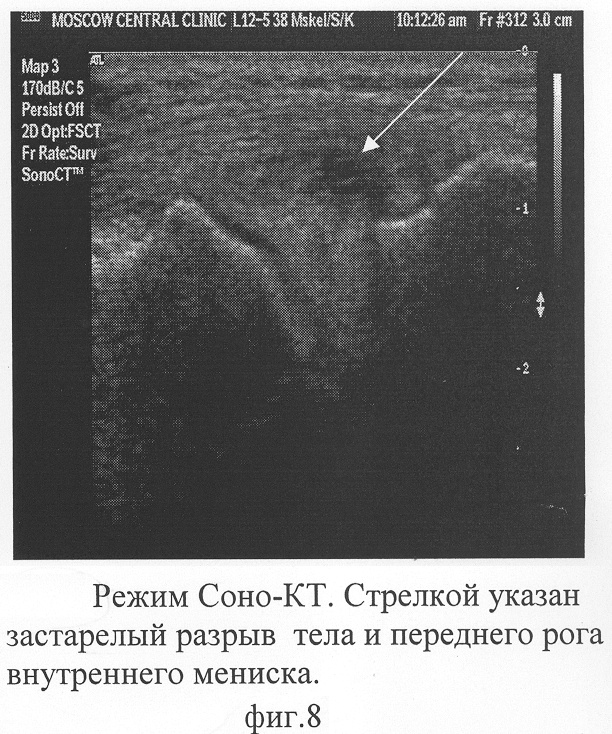

Выполняют УЗИ в последовательности. Укладывают пациента на спину. Определяют ориентиры: линию 11 пересечения дистального отдела медиального мыщелка бедренной кости; нижнего медиального полюса надколенника и проксимального отдела медиального мыщелка большеберцовой кости. По указанной линии 11 устанавливают линейный датчик, включают рабочую частоту равную 7 МГц. Согласно данным табл. №2 устанавливают параметры В-режима. Не меняя положения датчика по линии пересечения дистального отдела медиального мыщелка бедренной кости и нижнего медиального полюса надколенника, пациенту сгибают ногу в коленном суставе под углом 45°. Поворачивают датчик по часовой стрелки на угол 30° до появления на экране монитора переднего рога внутреннего мениска. Ротируют датчик, наблюдают на мониторе структуру тела внутреннего мениска, фиг.7. Структура переднего рога и тела внутреннего мениска неоднородная. Наблюдают локальный гипоэхогенный участок с единичными кальцинатами. Данное изменение свидетельствует о наличии патологических изменений. Предварительно диагностируют застарелый разрыв мениска.

Выполняют визуализацию переднего рога и тела внутреннего мениска, фиг.8. Диагностируют: застарелый разрыв переднего рога внутреннего мениска, распространяющийся на тело и его паракапсулярную часть.